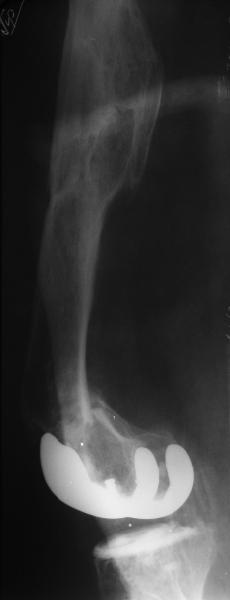

Глубокоуважаемые коллеги, Мужчина 41 года поступил с повторным (предыдущий в 2001 г.) переломом (3-недельной давности) над протезом коленного сустава.

В 1994 множественная травма, в том числе открытый перелом надколенника, осложнившийся гнойным артритом, и на этой же стороне перелом диафиза бедра (лечили в аппарате). В 1998 г. выполнено эндопротезирование коленного сустава.Предыдущий перелом (3 года назад) лечили консервативно, сросся при неустраненном смещении дистального блока бедра кзади ~ на 1 см.Амплитуда движений в коленном суставе перед последним переломом была ~90 градусов. Ходил без дополнительной опоры.Снимки в приложении. Какие будут предложения по поводу оперативного лечения в нынешней ситуации? У нас споры между ретро- и антеградным закрытым интрамедуллярным остеосинтезом.

A male 41 years old transferred to our unit with 3 week old femoral fracture near the knee prosthesis after a mimimal fall. In 1994 he sustained multiple injury with open patella fracture (complicated with septic arthritis), and ipsilateral femoral shaft fracture treated by ex-fix. TKA performed in 1998. In 2001 he got a periprosthetic fracture which was treated nonoperatively and healed with ~1 cm dorsal displacement of the distal femoral block. Knee ROM prior the recent injury was about 90-95 degrees. He didn't use walking aid.Images attached. I request your suggestions regarding surgical options in the situation? We mostly discuss ante- vs retrograde closed nailing.